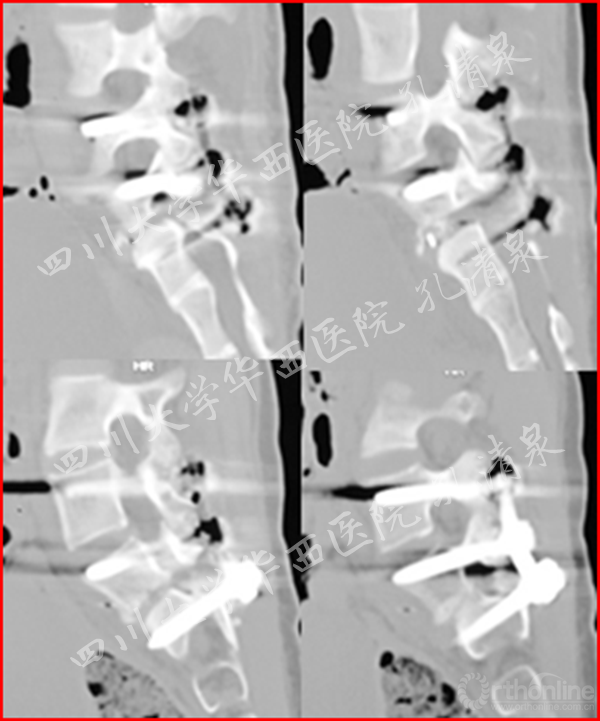

图5 术后矢状面CT重建显示复位情况良好

我们参考了四肢骨的骺板骨折的Salter-Harris分型,认为其骶1的骨骺滑移相当于Salter-Harris分型的一型损伤,分离一般发生在生长板的肥大层,故软骨的生长带留在骨骺一侧,所以多不引起生长障碍,且椎间盘的情况术前判断为正常,经过术中的再次验证,椎间盘情况良好,此病例行经后路腰5-骶1固定、腰5滑脱、骶1骨骺复位、椎管减压、后外侧植骨融合术,术后的情况验证了部分我们术前的认识,在术后7年的复查中,腰5骶1椎间盘信号尚可,腰5椎体和骶1椎的高度均得到2mm的生长,证明对于骺软骨的复位愈合以及椎间盘功能的保护是富有成效的。

治疗:经后路腰4-骶1固定、腰5滑脱复位、椎管减压、植骨融合术,术后患者左腿疼痛消失,术后复查侧凸残留17°,术后6月复查发现侧凸自发的减轻,术后两年复查时侧凸得到完全的矫正。